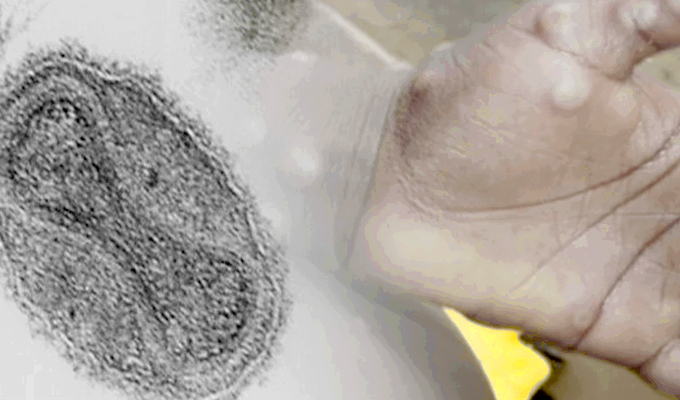

Los casos de personas infectadas con la viruela del mono están en aumento, aunque no con la velocidad con que la COVID-19 se expandió en el mundo; sin embargo, ya hay infectados en Reino Unido, España, Portugal, Estados Unidos, por mencionar algunos. Por ello, el Ministerio de Salud (Minsa) informó que mañana 20 de mayo declarará la alerta sanitaria ante la posible llegada de esta enfermedad.

Es una enfermedad endémica en África central que tiene como principales síntomas fiebre, malestar general, dolores musculares, inflamación de los ganglios linfáticos, escalofríos. Además, presenta la aparición de sarpullido en la cara y cuerpo. En las últimas semanas se han detectado varios casos en Europa y Estados Unidos por lo que se teme una posible propagación mundial.